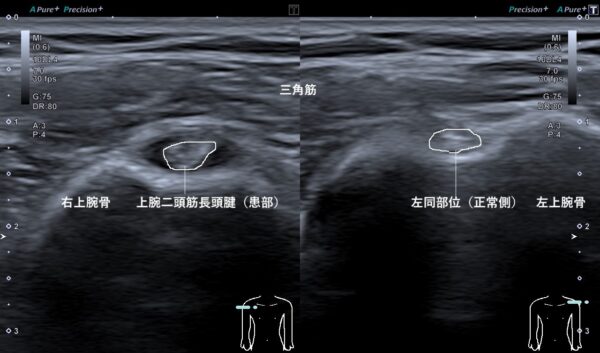

超音波(エコー)画像観察を行うと右上腕二頭筋長頭腱が左に比べて腫れて、その周囲は水(滑液)が過剰に溜まっていました(画像、白線で囲んだ丸の周囲の黒い箇所)。

このように上腕二頭筋腱が腫れてしまうのは、日常生活や仕事、スポーツなどで負担をかけ続けていると筋肉や腱が硬くなり、筋腱組織の収縮弛緩の機能が低下してしまいます。

すると硬くなった組織に強い収縮力が加わると、筋肉では肉離れ、腱では断裂などの損傷が起きてしまいます。